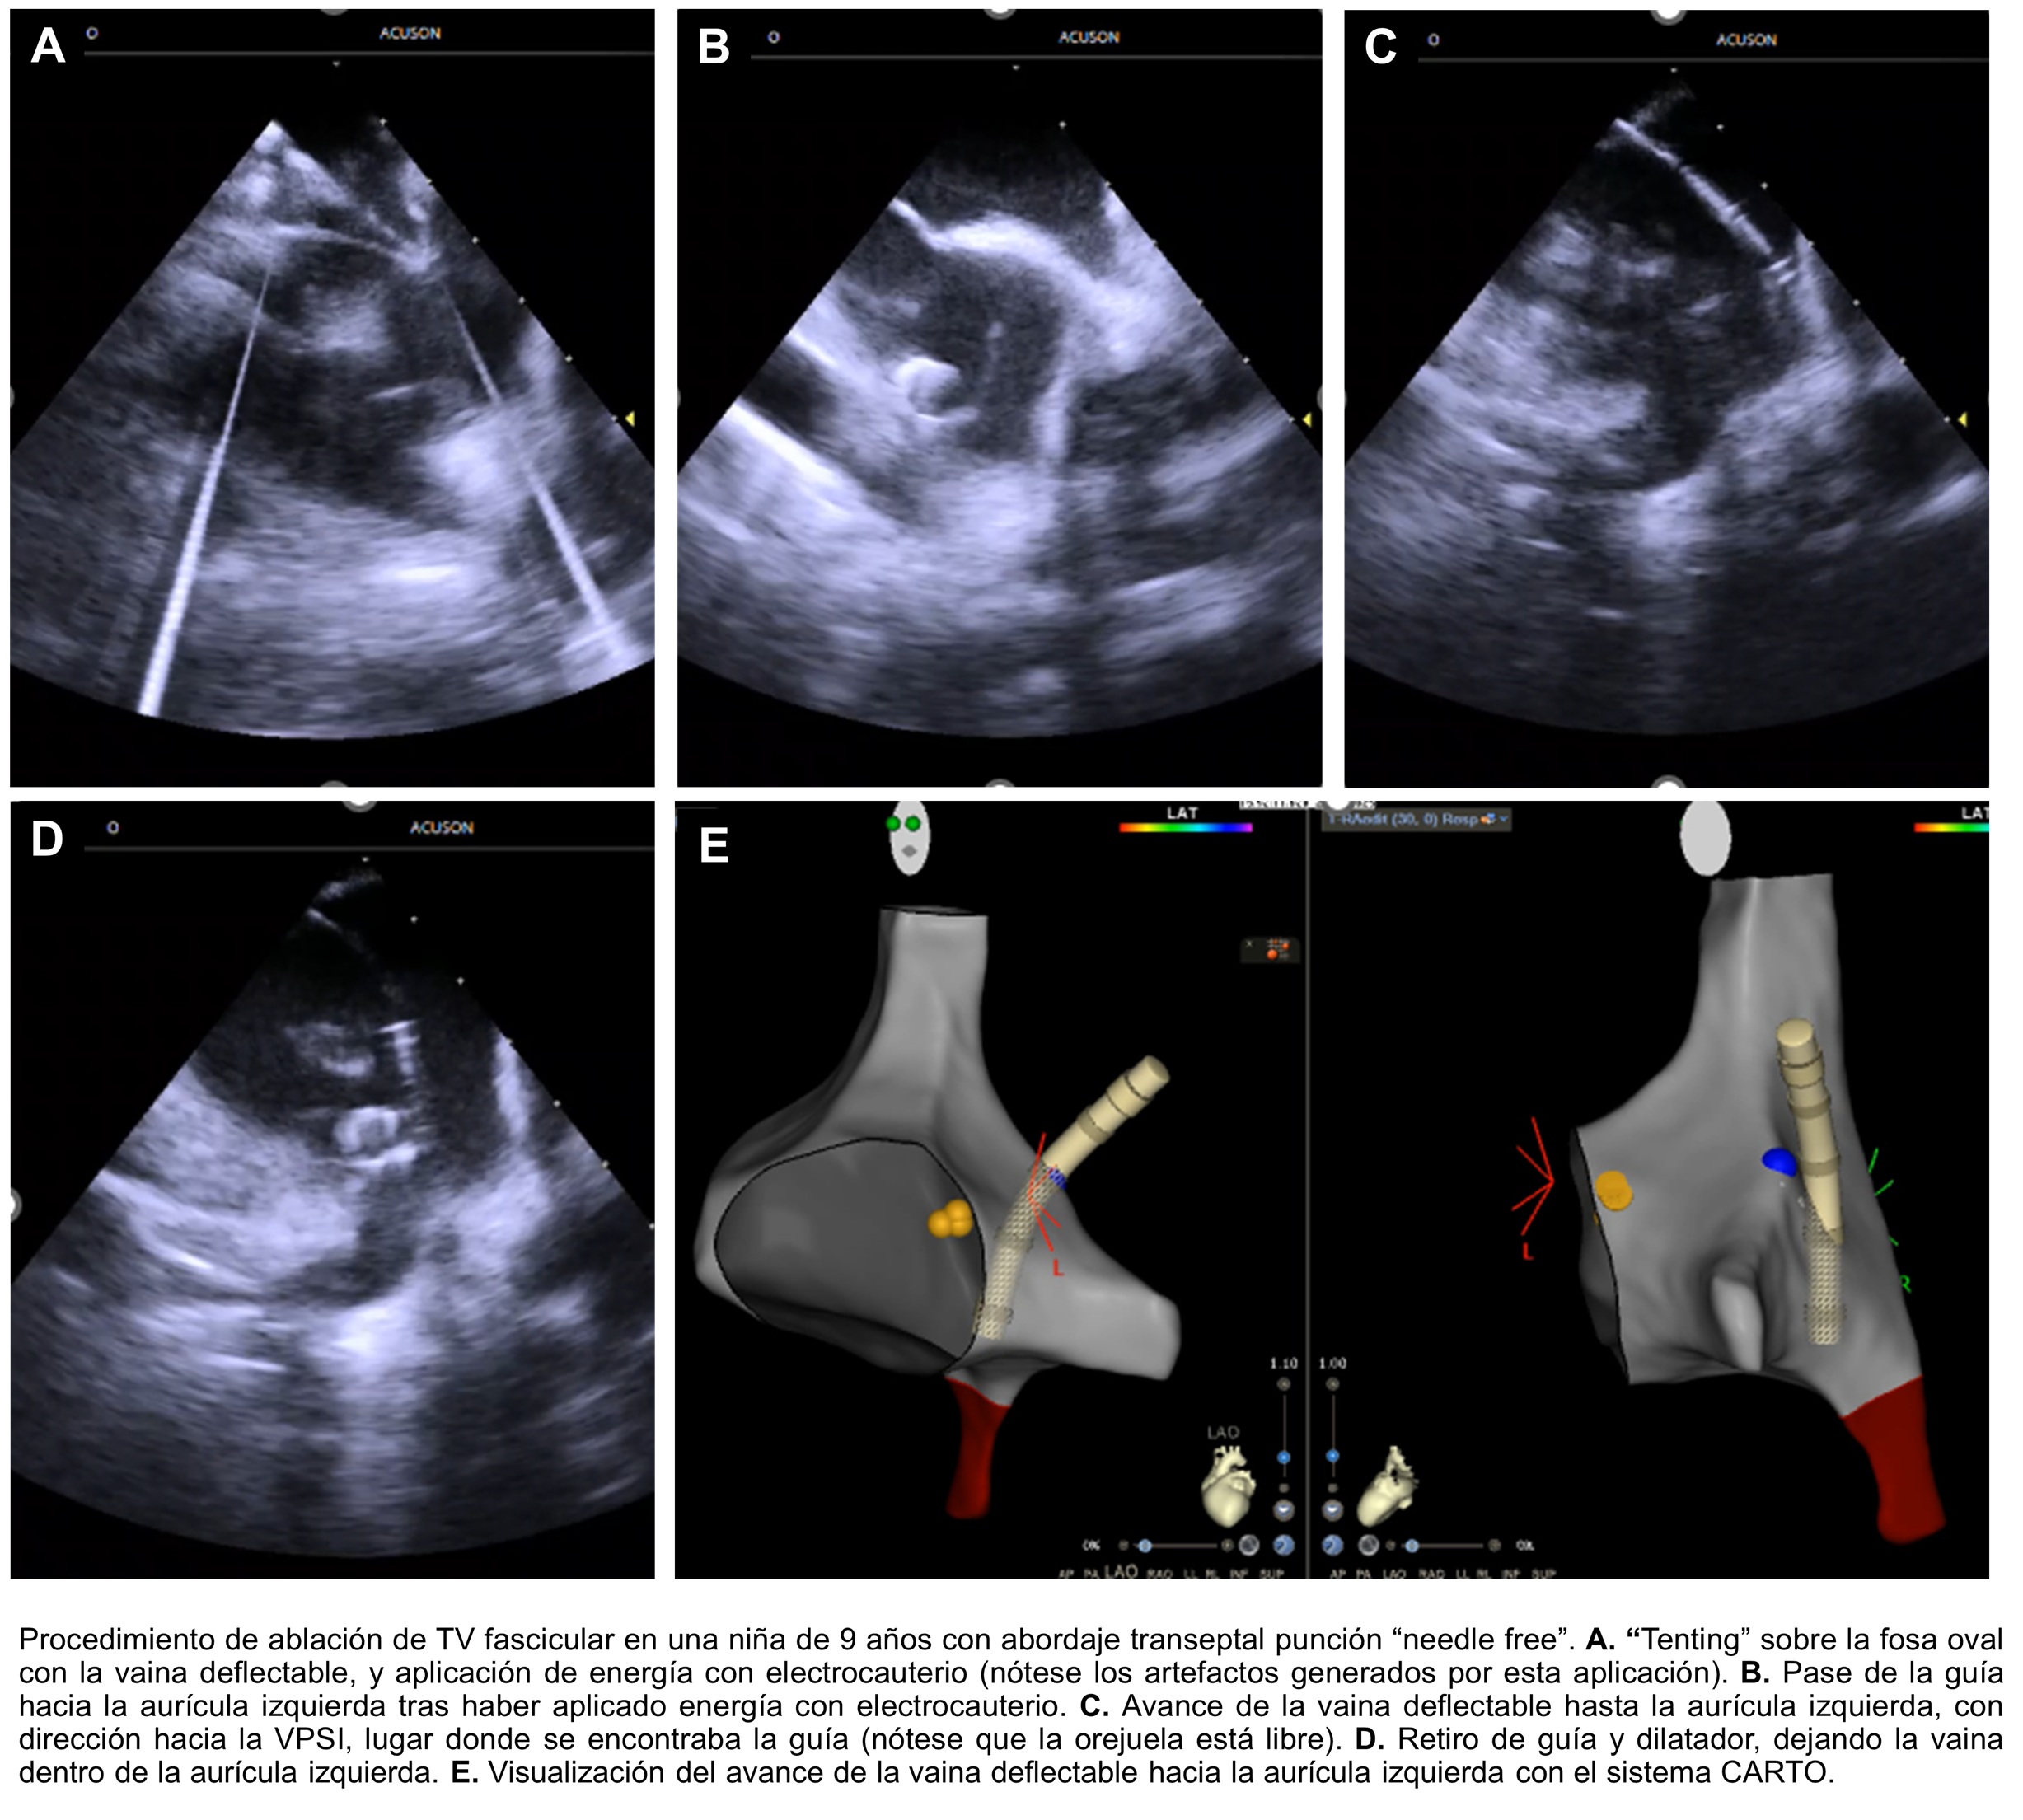

Introducción: La punción transeptal es un abordaje muy útil y muchas veces in...

Introducción La punción trans septal es un procedimiento usual en el abordaje...

INTRODUCCIÓN La punción transeptal (PTS) es un paso fundamental para la ablac...